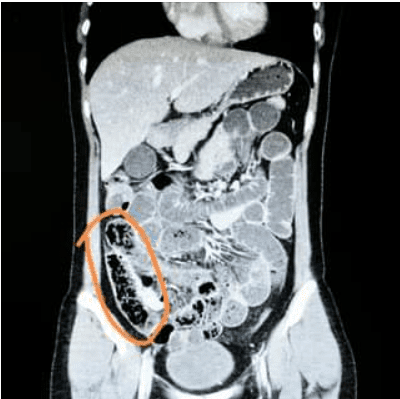

Seeing how dire the siutation was, doctors brought her in for an x-ray and found that her small intestines were completely blocked.

The x-ray above was also included in the doctor’s post on Facebook, circling out what must be the enoki mushrooms that clotted her small intestines.